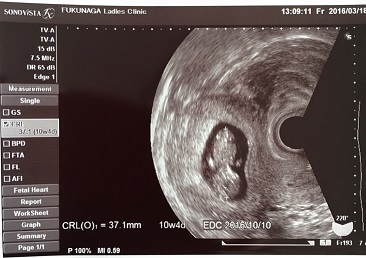

10週3日(10w3d・男の子)|りくえもん さん(32歳)

エコー写真撮影時のエピソード:

チョコレート嚢胞を患い、自然妊娠は難しいと言われ、体外受精を行なっていました。

昨年の秋に7週で稽留流産を経験し、今回上手くいかなかったら、嚢腫摘出手術をすると決めて挑んだ移植で、無事心拍確認ができました。

ただ、前回のこともあり、胎嚢確認ができても心拍確認ができてもまだまだ不安でしたが、このエコーで手足をもぞもぞさせて元気に動いている姿を確認し、やっと安心できました。